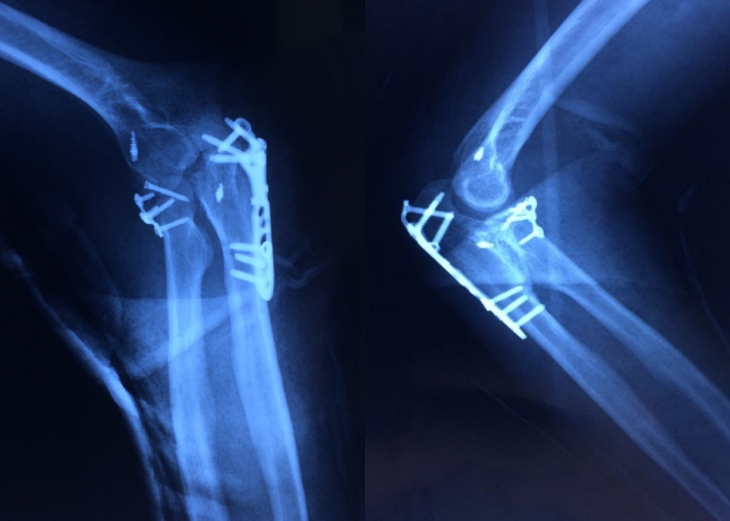

6月4日,骨卫士2020年学科规划建设第七期——病例讨论会在骨卫士专家委员会秘书处的精心部署下成功展开,本期病例讨论会围绕一则“创伤性肘关节不稳定”病例进行深入探讨。专家介绍骨卫士特聘专...